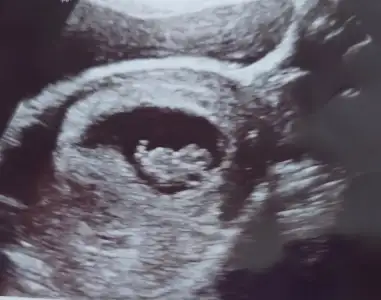

Ultrason karındansa kız, vajinal ise erkekArkadaşlar bu teorilerden anlayan var mı :) benim bebiş sizce cinsiyeti ne görünüyor teorilere göre :)

Karından :) neye göre tahmin ediliyor pekiUltrason karındansa kız, vajinal ise erkek![]()